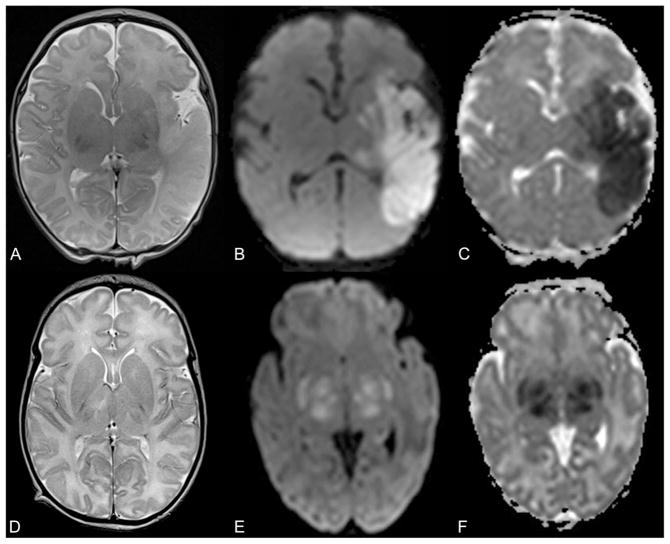

A pediatric neuroradiologist (A.P.) reviewed all brain MRI studies including conventional (T1- and T2-weighted) sequences as well as diffusion tensor imaging (trace of diffusion and apparent diffusion coefficient maps). Arterial ischemic stroke was diagnosed when an ischemic lesion (restricted diffusion including bright signal on trace of diffusion and low apparent diffusion coefficient values) was visualized in the vascular territory of the anterior, middle, or posterior cerebral arteries (Fig. 1A–C). Because we used diffusion changes as a criterion for the imaging diagnosis of stroke, and diffusion-weighted imaging changes typically normalize within 10–14 days after injury, this lets us time stroke to within 10–14 days previous to the MRI study.9 Magnetic resonance imaging abnormalities diagnostic of hypoxic–ischemic encephalopathy were focal or diffuse hyperintense T2 signal with or without changes in diffusion characteristics in cortical gray matter, subcortical white matter (Fig. 1D), basal ganglia (Fig. 1E–F), thalami (Fig. 1E–F), and hippocampi. Hypoxic–ischemic injury in a para-sagittal or watershed distribution was classified as gray and white matter abnormality in the territories of the anterior and middle or middle and posterior cerebral arteries, respectively. Hypoxic–ischemic injury in the perirolandic region was classified as gray and white matter abnormality in the territory of the middle cerebral artery. Periventricular white matter injury was classified as changes in signal intensity or diffusion of the white matter within the middle cerebral artery territory.

Fig. 1.

Axial T2-weighted magnetic resonance (MR) image (A), trace of diffusion map (B), and apparent diffusion coefficient (ADC) map (C) of a 3-day-old neonate with arterial ischemic stroke show hyperintense T2 signal of the cortical gray and subcortical white matter within the vascular territory of the left middle cerebral artery with absence of the normal cortical T2-hypointese signal and matching bright signal on trace of diffusion map and low ADC values (dark on C) representing restricted diffusion in the infarcted brain tissue. Axial T2-weighted MR image (D) of a 9-day-old neonate with hypoxic–ischemic encephalopathy and hypothermia therapy reveals global T2-hyperintense signal of the cerebral white matter. Axial trace of diffusion map (E) and ADC map (F) of a 6-day-old neonate with hypoxic–ischemic encephalopathy and hypothermia therapy show bright signal within the bilateral basal ganglia and thalami with matching low ADC values (dark on F) representing cytotoxic edema.